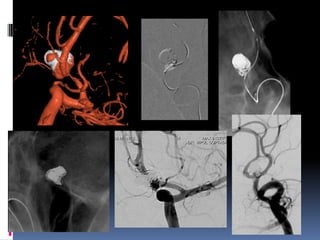

Parent vessel occlusion-Cavernous ICA, dissecting (VA), small peripheral

Fusiform, dissecting aneurysm

Parent vessel occlusion-CavernousICA, dissecting (VA), small peripheral